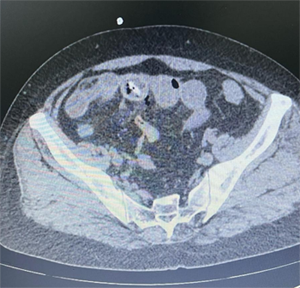

原来,老人当天凌晨突然出现了下腹部疼痛,并持续加重,继而出现发热症状。按照就诊流程,首先就诊于回龙观院区发热门诊,排除新冠肺炎的可能。老人腹部CT检查提示,小肠可见高密度影,并已穿破肠壁,周围有异常气体影,肝周和盆腔可见积液。医生再次追问病史,老人讲述近几日进食了大枣,但已记不清而是否将枣核也一并吞下。了解病情后,柏楠主任医师、吴全副主任医师和崔爱民主治医师果断决定完善相关术前检查,收入院给予急诊手术治疗。

术前的腹部CT